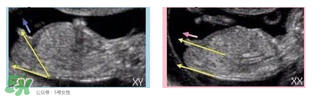

必須要NT超圖全景,可以看到下半部分的B超圖片才能判斷。外國人稱這種判斷法為nub theory。

主要通過尾椎那里判斷。 為了讓大家更直觀一些,我找兩個比較明顯的圖,男左女右,大家看男孩兒的特征點與身體呈45度角,還多一些,而女孩兒的特征點幾乎和軀體平行。圖第一張男寶,第二張女寶

用線條表示一下就更直觀了.當然,這也不是完全絕對的,如果你們發(fā)現(xiàn)自己的寶貝兒與心想的不一樣,那這理論不一定對,不是絕對的.千萬不要因為這個而影響自己孕期心情,寶寶健康是第一位的,我只是把自己所了解到的知識給大家普及一下。